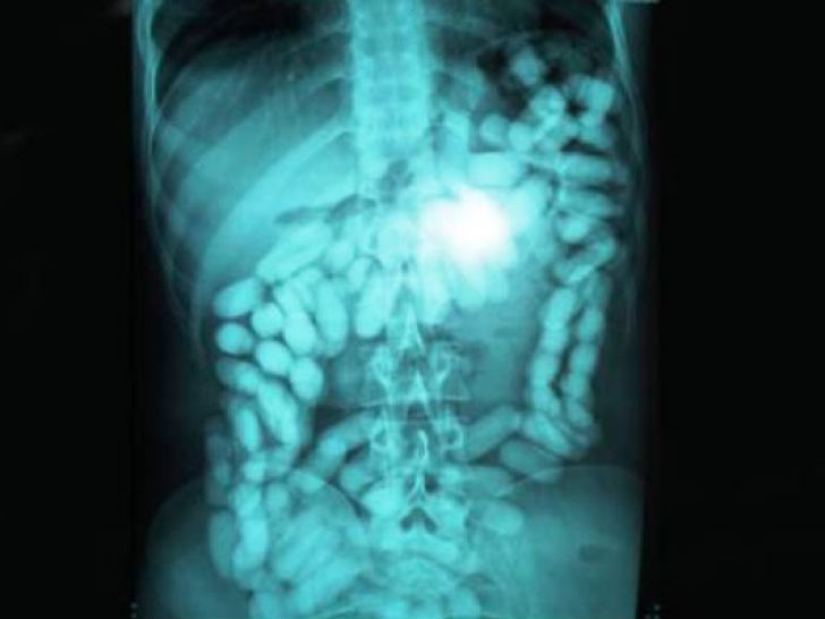

And this is the picture of a man who swallowed a considerable amount of drugs in order to smuggle them across the border.